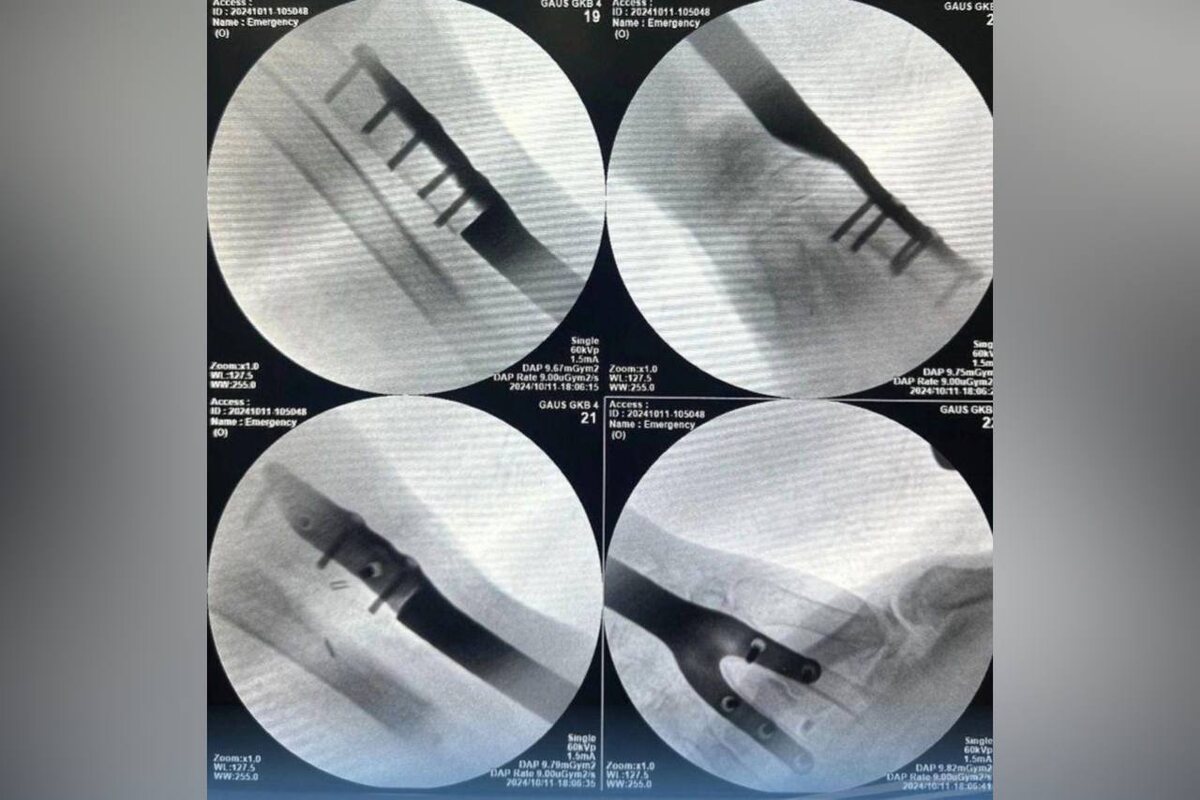

В Оренбурге 72-летней пенсионерке после нападения собаки установили имплант в руку, сообщили в Оренбургском центре хирургии и травматологии.

Женщину госпитализировали с укусом раны предплечья и фрагментарными переломами в Оренбургский центр хирургии и травматологии.

Ей обработали рану, наложили стержневой аппарат, а также сделали прививку от бешенства и курс антибиотиков. После пенсионерке сделали компьютерную томографию здоровой руки и установили индивидуальный имплант лучевой кости левого предплечья на основе снимков. Имплант прижился, а рана зажила. Женщина чувствует себя хорошо.